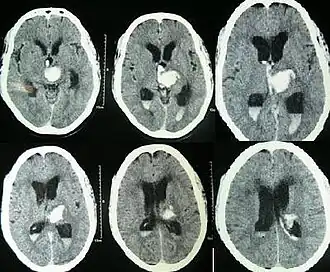

Hydrocephalus as seen on a CT scan of the brain. The black areas in the middle of the brain (the lateral ventricles) are abnormally large and filled with fluid.

Spontaneous intracerebral and intraventricular hemorrhage with hydrocephalus shown on CT scan[31]